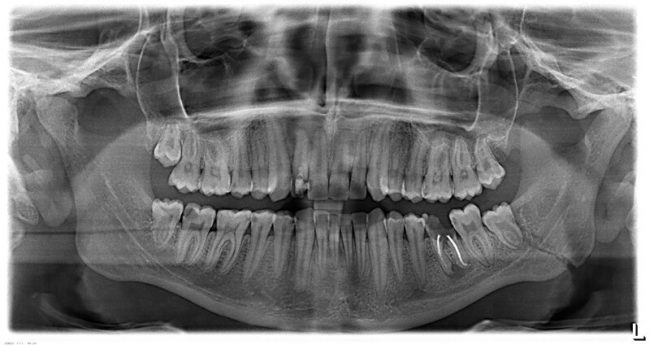

3. После протезирования (временного или постоянного)

А вот это  — совсем большая редкость:

Если имплантат дошёл до протезирования, если позволил установить на себя коронку, то риски того, что он расшатается и выпадет, крайне малы. По факту, мы встречаемся с подобными ситуациями не чаще раза в год (если мы говорим именно о потере имплантата).

Существует два варианта развития «отторжения», принципиально разных по своей природе.

Первый вариант связан с упоминавшейся ранее фиброинтеграцией, когда в силу особенностей макродизайна имплантат довольно прочно удерживается в костной ткани и позволяет зафиксировать на него коронку. Однако в последующем, под жевательной нагрузкой появляется подвижность имплантата, что и приводит к его потере.

Симптоматика в этом случае может быть довольно противоречивой: от «совершенно не беспокоит» до «постоянный дискомфорт». При снятии оттисков, фиксации трансфера, абатмента или коронки, пациент говорит, что «чувствует имплантат», но без болезненности. Как правило, боль появляется только на финальных стадиях, при значительной подвижности.

Рентгенологическая картина также не однозначна: от «ничего не видно» до значительной деструкции костной ткани вокруг имплантата:

Причины — те же, что и в предыдущем случае: хроническая компрессионная травма окружающей имплантат костной ткани избыточным торком, изредка — ожог из-за отсутствия адекватной ирригации. Но в силу особенностей макродизайна, а именно, благодаря развитым антифрикционным и/или антиротационным конструктивным элементам, имплантат не проворачивается даже при значительном (до 40 Нсм) усилии. Это затрудняет диагностику фиброинтеграции на ранних стадиях.

Второй вариант, как уже упоминал, развивается по иному сценарию. Имя ему — ПЕРИИМПЛАНТИТ:

И о нём мы поговорим в следующей статье. Не переключайтесь!